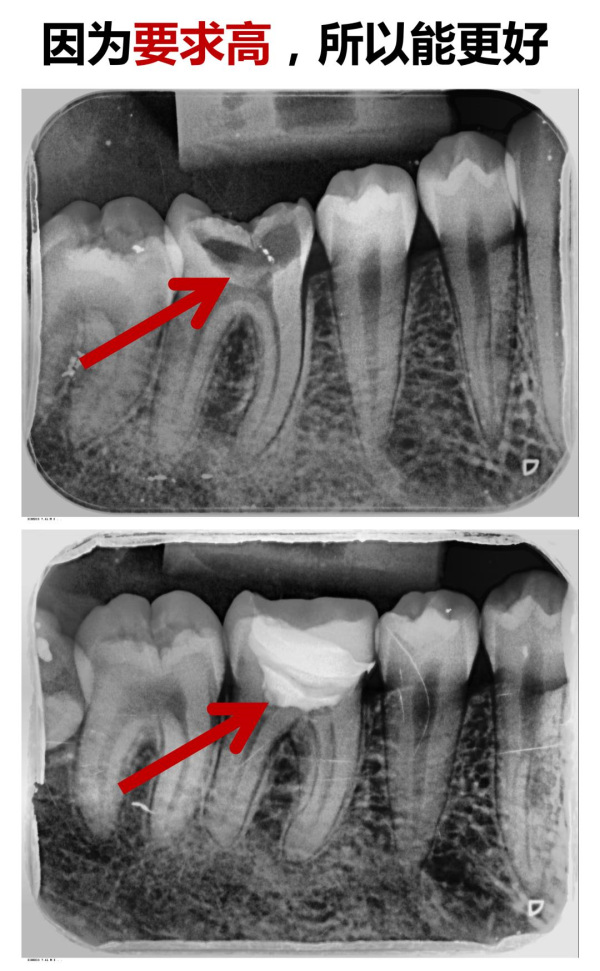

譚主任顯微案例實(shí)拍展示